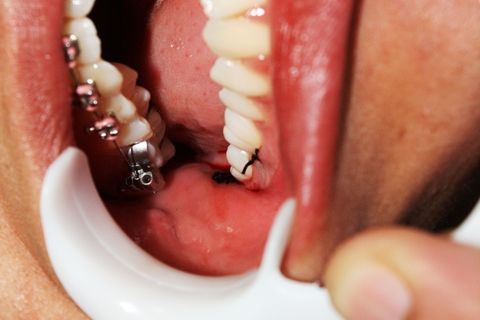

Paciente AB, sexo feminino, 19 anos, com indicação para exodontia dos elementos 18 e 48 incluso e mesio-incliniado.